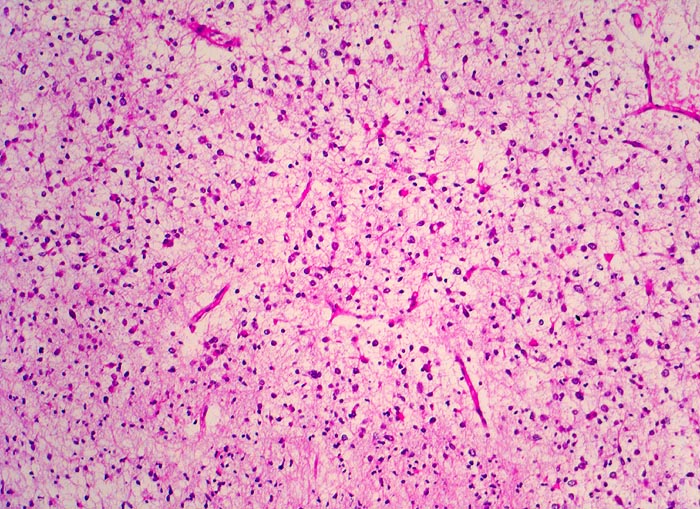

PathoPic ID 5252 - Oligodendrogliom (WHO Grad II)

Oligodendrogliom (WHO Grad II)

maligner Tumor

Hirn frontal

Nervensystem

Typisches dichtes Netzwerk verzweigender

Kapillaren.

Kopfschmerzen und epileptische Anfälle seit zwei Jahren.

Histologie

100